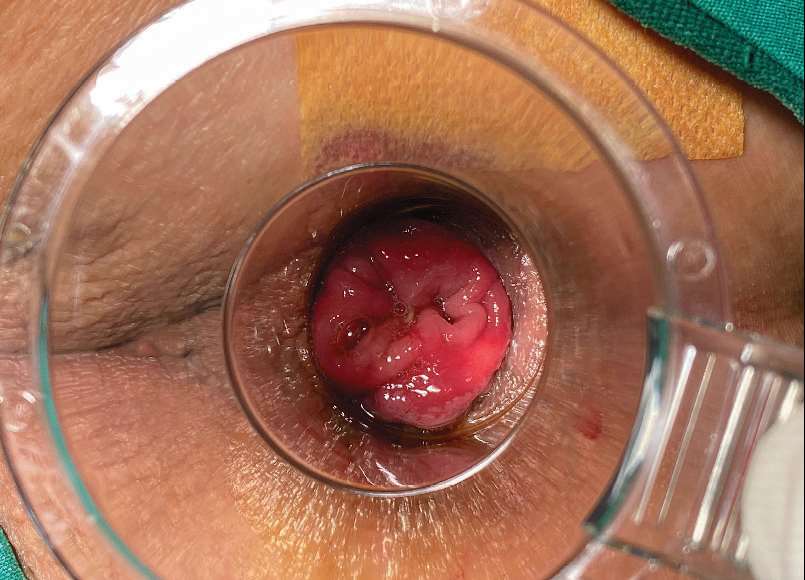

(1)血管肿型:由毛细血管增生扩张而成,表面粗糙而柔软,色鲜红,痔体与周围黏膜分界较清楚,痔体多数较小,可见小出血点或浅表糜烂,易出血(图 2—5,图 2—6)。

图 2—5 血管肿型内痔(1)

图 2—6 血管肿型内痔(2)